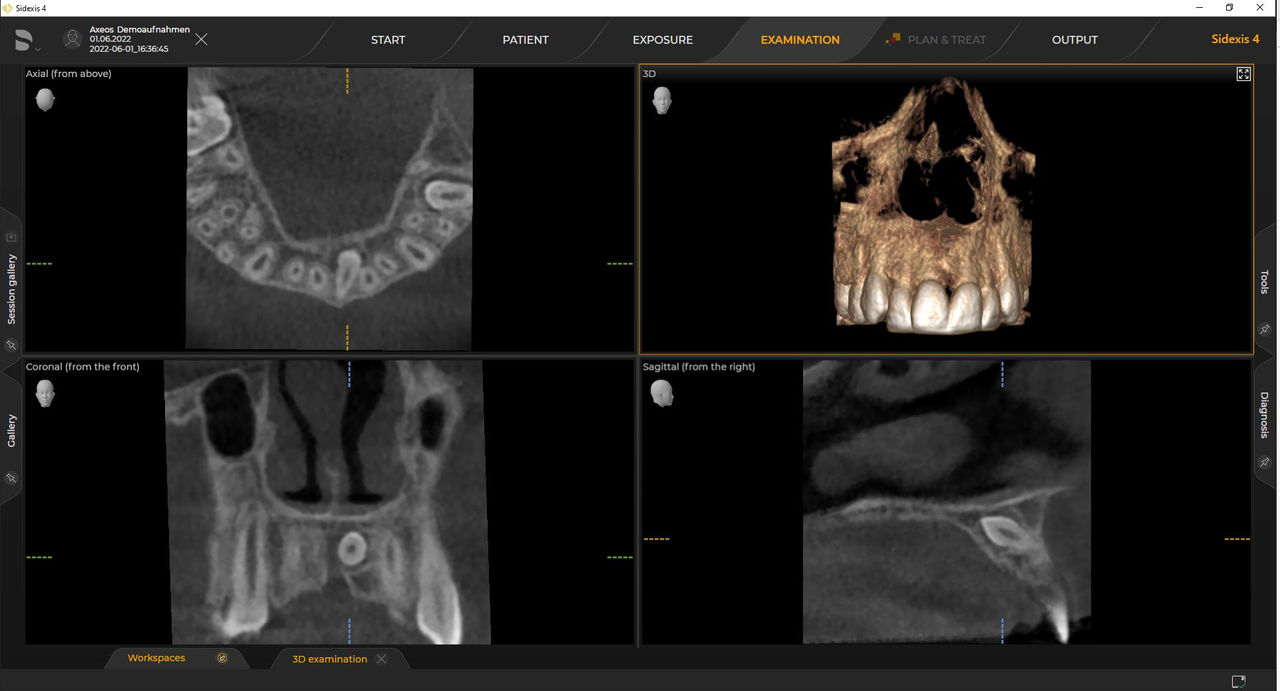

Los requisitos siguen aquellos del software de procesamiento de imágenes de Sidexis 4 y Axeos. Para obtener más detalles, consulte los requisitos del sistema Sidexis 4 y los requisitos de instalación de Axeos.

Las unidades 3D de Dentsply Sirona funcionan exclusivamente con Sidexis 4. Sin embargo, la migración de datos de Sidexis XG a Sidexis 4 es muy fácil. Sidexis 4 permite una experiencia digital completa con las últimas herramientas.